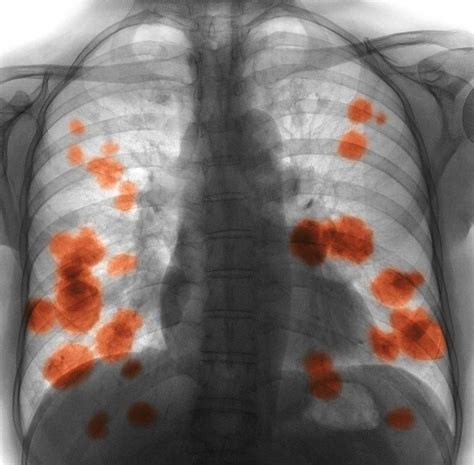

The symptoms of Krankheit X include fever, chills, muscle aches, fatigue, and headaches. The virus can also cause severe respiratory problems, kidney failure, and liver failure.

- Symptoms: Fever, headache, hemorrhaging, and organ failure.

| Symptoms | Fever, cough, shortness of breath, organ failure |